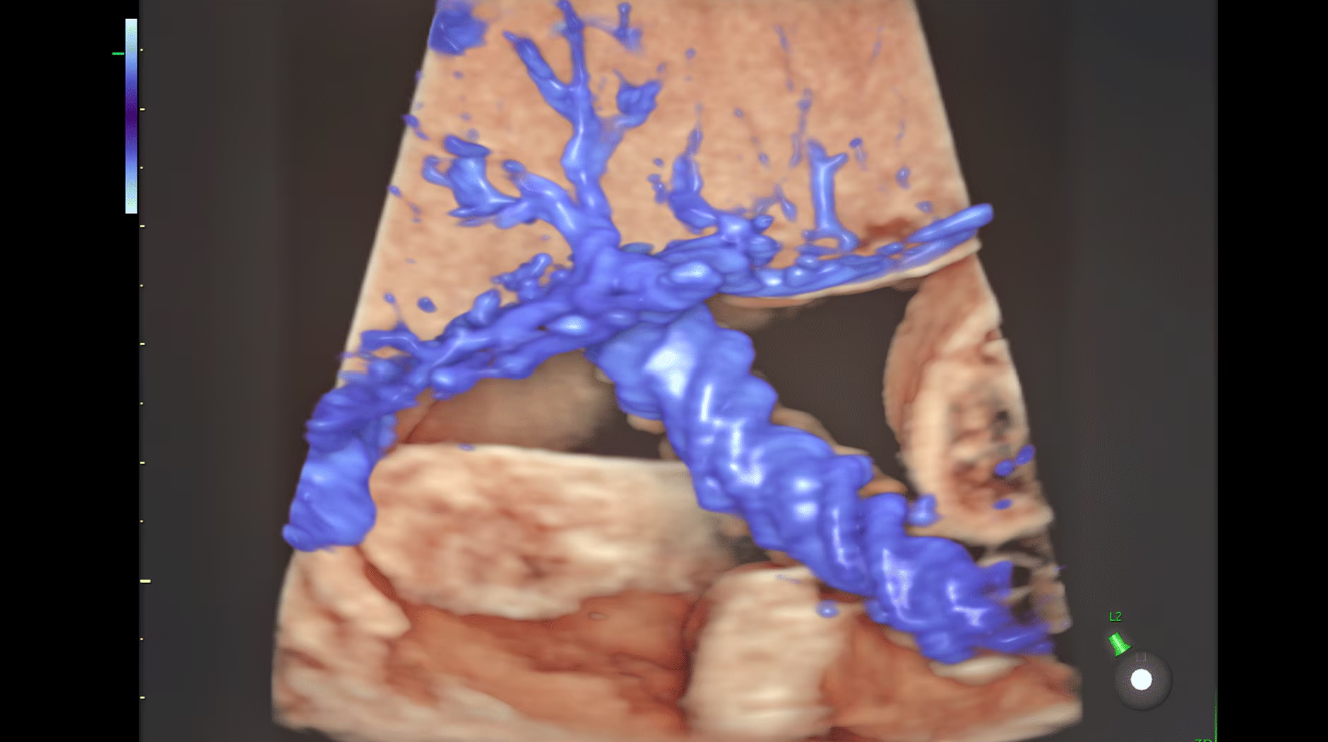

Пуповина и плацента с помощью Slowflow3D и HDlive